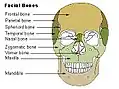

Formato com detalhes em inglês

Formato com detalhes em inglês -